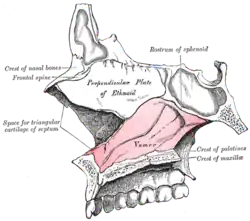

Ossos e cartilagens do septo do nariz. Lado direito.

Ossos e cartilagens do septo do nariz. Lado direito. -